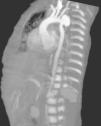

Durante la realización del primer ecocardiograma doppler se observa dilatación de aorta descendente, corroborado en estudio ecocardiográfico posquirúrgico de reparación de DAP, con aneurisma en arco aórtico posterior a la arteria subclavia así como presencia de trombo de 4x3cm en la desembocadura de vena cava superior; se realiza angiotomografía en la cual se observa aneurisma a nivel aórtico, probable coartación aórtica, además de aneurisma en aorta abdominal (fig. 1). Al momento del diagnóstico se encuentra con recuento leucocitario y plaquetario normal, anemia, hipocomplementemia a expensas de C3, PCR positiva y factor VIII aumentado.

Al realizar ecocardiogramas de control por la patología cardiaca de base, se nota la dilatación en aorta, siendo más evidente en la 3.a semana de vida, debido a este hallazgo se decide la realización y confirmación en angio-TC (fig. 2).